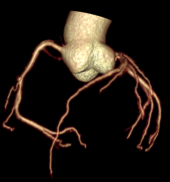

Chẩn đoán hình ảnh mô mềm tiên tiến cho vùng bụng.

Tăng cường độ tương phản I-ốt.

Đảm bảo hình ảnh chất lượng cao.